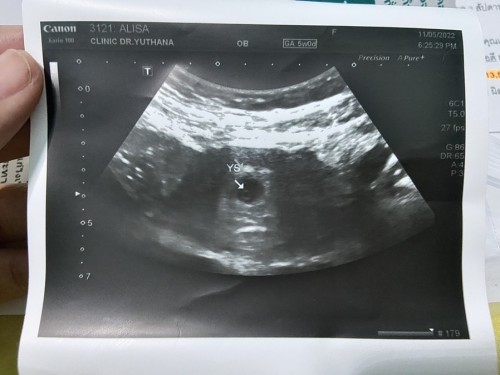

ท้องแรก5วีคค่ะ

กลมๆข้างในถุงคืออะไรคะที่ลูกศรชี้อยู่ช่วยดูหน่อยจ้า

ถุงไข่แดงรึป่าวคะ เป็นถุงอาหารของตัวอ่อน ที่ใช้ในไตรมาสแรก 1-3 เดือนค่ะ น้องจะได้รับสารอาหารจากถุงนี้

กลมๆคือถุงไข่แดงค่ะ